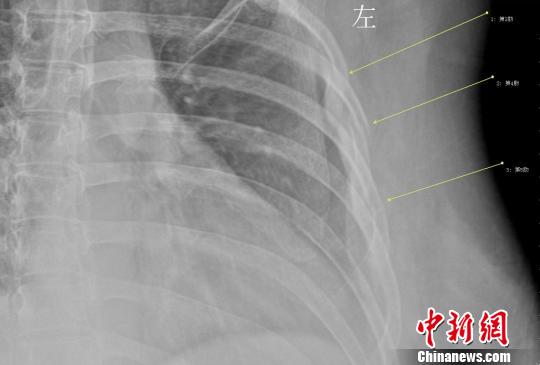

年輕女白領因咳嗽導致三根肋骨骨折 劉姍姍 攝

拍片結果顯示,她的第3、4、5肋骨骨折,胸外科醫生給她上了胸帶固定,并給予了止咳鎮痛的藥物治療。胸外科徐家行醫生詳細詢問病史,在排除了其他因素后,考慮還是咳嗽引起的肋骨骨折。